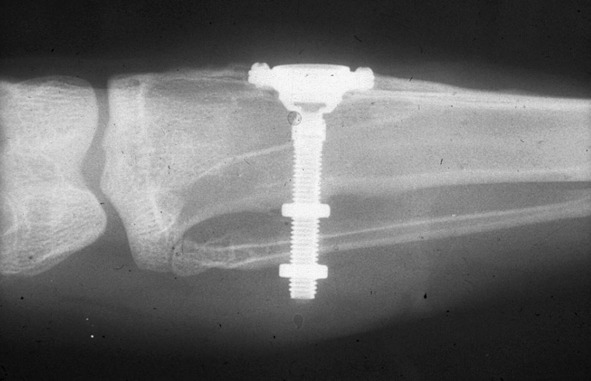

Начиная с 1952 года, швед Ингвар Бранемарк (P.Branemark) проводил исследования, в области остиоинтеграции – соединения костей с помощью металлических элементов. Он попробовал заменить элементы из нержавеющей стали на титановые, которые были легче и прочнее. Бранемарк попытался использовать их для соединения сломанных костей, но он столкнулся с проблемой: титановые элементы прочно соединялись с костями и после заживления раны их было невозможно удалить. В течение 13 лет он безуспешно пытался применять титановые элементы в остеоинтеграции, пока не нашел титану другое применение. Титановые импланты стали блестящим решением для протезирования зубов. Главный недостаток титановых имплантов стал их достоинством. Импланты из титана сращивались с челюстной костью и становились надежной основой для зубных протезов.

Сейчас это самый надежный метод протезирования зубов.

Рисунок 46. Остиоинтеграция

Рисунок 47. Титановые импланты